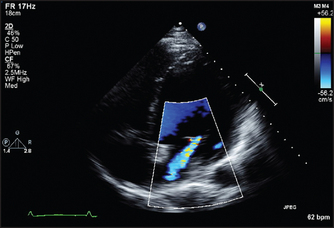

• In colour flow mapping, it is possible for echo machines to solve the Doppler equations for sectors of the two-dimensional scan in real time, assign a colour code depending on the direction and velocity of flow and superimpose this on the two-dimensional image. In this way, flow within the heart is visible in relation to the anatomy and abnormal jets of blood can be more easily detected (see Figure 8.18).

Sector scanning and M mode pictures can provide information about valve morphology, for example thickening or prolapse of the leaflets (see Figure 8.17). Doppler echo can reveal abnormal jets of blood, for example regurgitant jets, and measure flow velocity across valves. This measurement can be used to estimate the valve gradient (the difference in pressure across the valve).

3. Mitral regurgitation and mitral valve prolapse. Here the mitral valve may appear abnormal and abnormal coaptation of the leaflets may be visible (see Figure 8.17).

5. Aortic regurgitation. The valve may look thickened or occasionally a cusp may be seen to prolapse (see Figure 8.20). The aortic root size may be increased, especially if this is the cause of the aortic regurgitation. Left ventricular dilation is often present and the size of the ventricle may be used as an indication of severity. Doppler interrogation will show the regurgitant jet for a variable distance into the left ventricle.